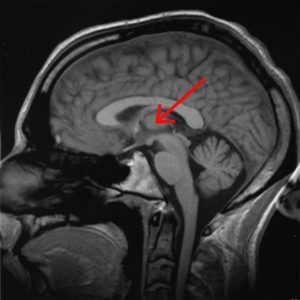

Thalamus